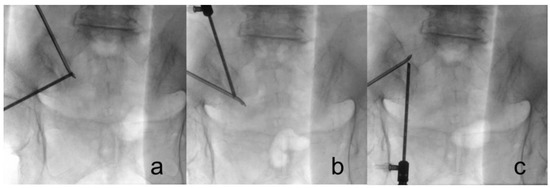

After sterile preparations and draping, an anteroposterior fluoroscopic view was obtained using a C-arm. A transducer was tilted cephalad at 10°–15° to optimally visualize the posterior aspect of the SIJ. We marked the S1–S3 foramina and the SIJ line under fluoroscopy (Figure 1a). Skin entry points for the viewing portal and working portal were positioned at 0.5 cm medial to the SIJ line and at the level of the S1 and S2 foramina, separately. We set the S1 incision as the working portal and the S2 incision as the viewing portal (Figure 1b).

We attempted to visually confirm the lateral branches exiting the sacral foramina and the branches coursing toward the SIJ to ensure accuracy during nerve lesioning (Figure 3). Throughout the procedure, we maintained communication with the patient to assess the pattern and location of pain. We asked the patient if the pattern and location of SIJ pain were associated with each stimulus and to identify which stimulus area caused the most pain. After ablation of the target points, the endoscope and cannula were removed, and the wound was closed with 3-0 nylon simple interrupted sutures (Figure 1d)

Figure 3. Fluoroscopes were used to guide the ablation point. (a) S1 foramen; (b) S2 foramen; (c) L5 dorsal ramus, which is located at the junction of the sacral alar and promontory.